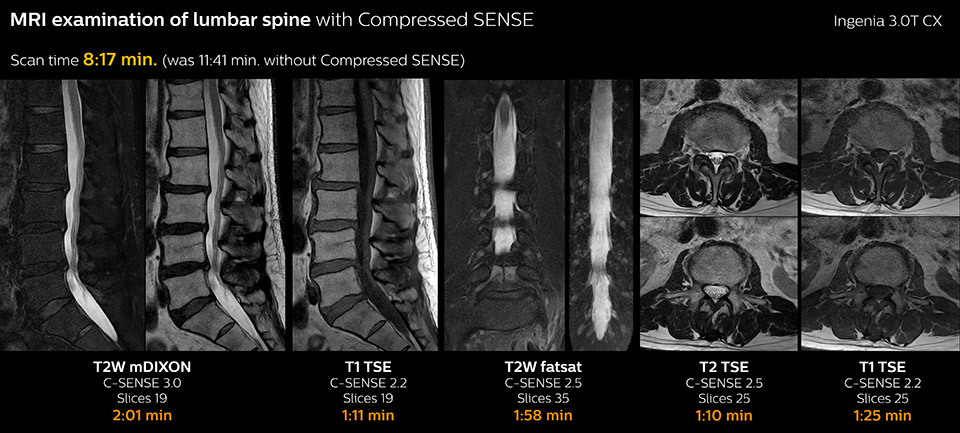

Fast MRI of lumbar spine

which corresponds to 34% reduction.

With Compressed SENSE, the scan time for the routine lumbar spine examination at KNC was reduced from 11:41 to 8:17 minutes,

MRI examination of the lumbar spine with Compressed SENSE

Ingenia 3.0T CX

Scan time 8:17 min. (was 11:41 min. without Compressed SENSE)